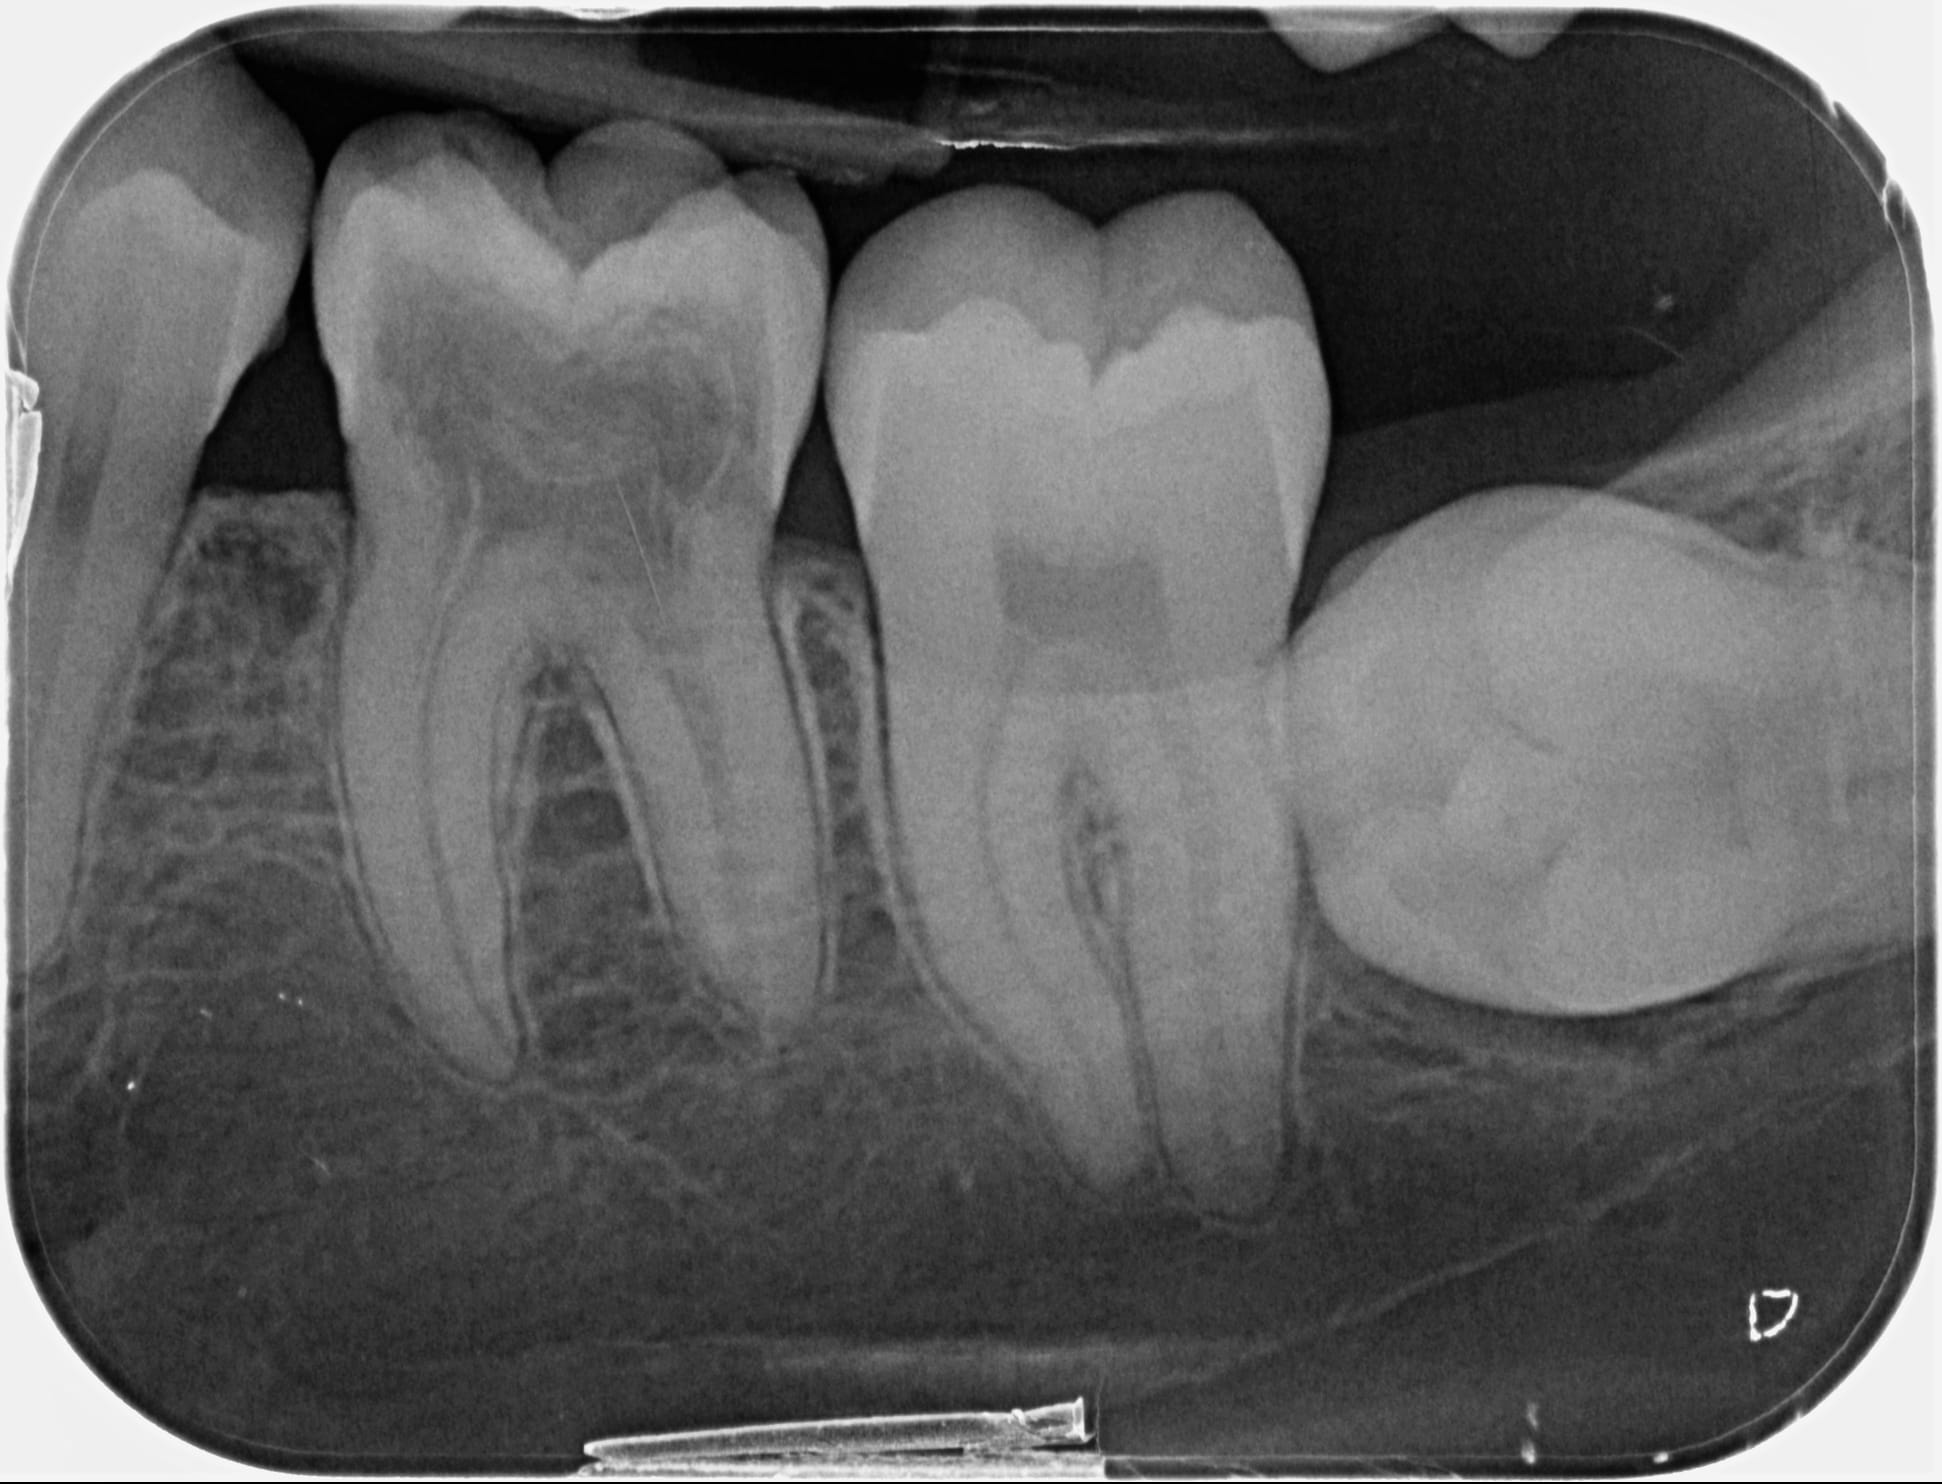

patiente envoyée par ortho car dent "rose". J'ai mis la radio. L'image est un peu bizarre je trouve et pas d'effraction de l'émail nul part..

On dirait plutôt une résorption interne mais çà ne touche pas la racine..

Vos avis ? "pink spot" ?

Résorption externe !!! A l'origine du pink spot. La dent n'est plus qu'une coquille vide.

Ca a l'air très avancé quand même... il faut tout nettoyer et voir s'il reste asser de dent pour couronner !

Je suis peut être trop pessimiste, mais pour moi c'est davier et ensuite implant. Cela dit, ca ne mange pas de pain, en l'absence de symptôme, de laisser la dent sur l'arcade. Ca peut durer assez longtemps sans causer de souci. Juste contrôler qu'un abcès, meme relativement asymptomatique, ne se forme pas (ce qui compromettrait / endommagerait l'os dont tu vas avoir besoin pour le futur implant). Ta dent est en effet une coquille vide.